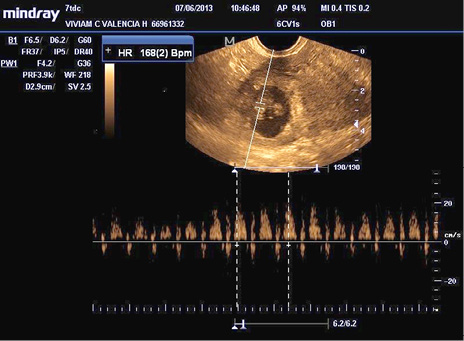

Mujer de 36 años, primigestante, sin antecedentes patológicos relevantes. Sin uso de método anticonceptivo desde su inicio de vida sexual, a los 27 años. La que consulta por cuadro clínico de 48 horas de evolución consistente en dolor abdominal tipo cólico asociado a sangrado vaginal en escasa cantidad, no acorde con la menstruación que presenta amenorrea de 13 semanas; dolor que progresa de leve a moderado en las últimas 12 horas, por lo que consulta. Ingresa caminando por sus propios medios. Al examen físico Tensión Arterial de 120/70 mmHg, Frecuencia Cardiaca de 78 por minuto, Frecuencia respiratoria de 16 por minuto y Temperatura 36.5ºC., abdomen doloroso a la palpación de hipogastrio, sin signos de irritación peritoneal. Examen ginecológico: vagina eutrófica, cérvix de aspecto sano, útero en Anteversoflexión, discreto aumento de tamaño, con dolor a la palpación y movilización de anexo derecho. Se solicitan paraclínicos: Hemograma: Glóbulos Rojos: 3750000/mm3, Glóbulos blancos: 10200/mm3, Hemoglobina: 13,5g/dl, Hematocrito: 37.8%; ß-hGC de 8.940 mUI/ml; Ecografía Transvaginal útero con endometrio engrosado y saco gestacional en cuerno derecho con feto vivo, biometría para 11.4 semanas (Figura 3). Se diagnostica: Embarazo ectópico cornual derecho no roto, y se le realiza una laparotomía exploratoria, confirmándose el diagnóstico y se procede a la realización de una resección cornual en cuña.

Figura%2013-3.jpg

Figura 3. Visión del saco gestacional y embrión en cuerno uterino derecho, diagnosticado en nuestro servicio.